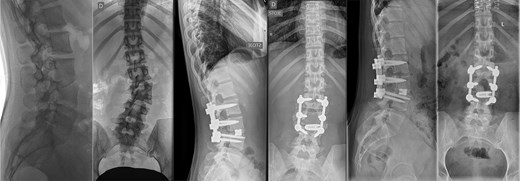

Last preoperative X-ray, lateral (A) and anteroposterior view (B). After 10 weeks of follow-up; lateral (C) and anteroposterior view (D). After 1 year of follow-up; lateral (E) and anteroposterior view (F).

The postoperative course was uneventful, with no evidence of neurological dysfunction. The patient commenced physiotherapy on the first postoperative day. At the initial follow-up, 10 weeks post-surgery, she was ambulating unassisted with reduced back and leg pain, without neurological impairment but with a persistent forward-leaning posture that remained correctable with verbal cues. At the final follow-up, one year after surgery, she reported resurgence of forward-leaning posture after longer walks, and referred to a tertiary rehabilitation institution. Imaging demonstrated L2–L5 fusion with no signs of instability or residual deformity (Fig. 1).